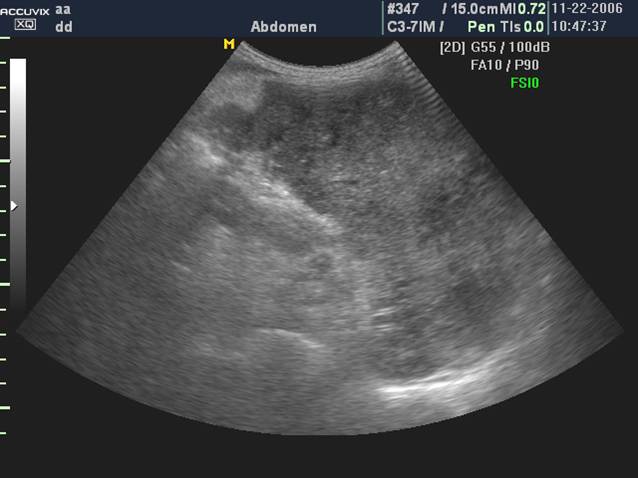

假性脾囊肿: